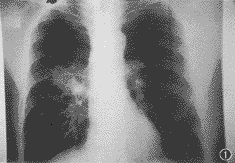

第35例——右肺门斑片状致密影